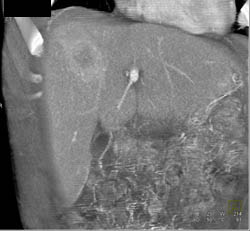

Focal Nodular Hyperplasia (FNH)